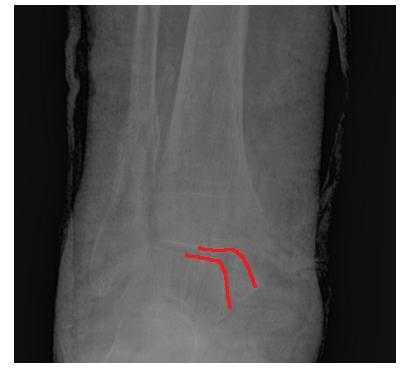

Пациент М. 1980 г.р., травму получил при падении на стопы с высоты 1,5 метра. Лечился по месту жительства (в травмпункте районной больницы) консервативно в гипсовой повязке в течение 14 дней. Консультирован в травматологическом отделении ФГБУ «УНИИТО им. В.Д. Чаклина» Минздрава РФ, предложено оперативное лечение. При поступлении кожные покровы стопы чистые, без признаков воспаления и сдавления тканей. Стопа отечна, уплощена. На рис. 1 представлены рентгенограммы пациента. Прооперирован через 2 недели после травмы. Операция состоит из двух этапов. Первый этап заключается в наложении дистракционного аппарата. Проводятся две спицы 1,8 мм во фронтальной плоскости: первая через нижнюю треть диафиза большеберцовой кости, вторая через бугор пяточной кости (рис. 2). Спицы фиксируются в дистракционном аппарате, выполненном из двух полуколец, соединенных между собой двумя телескопическими тягами. Особое расположение полуколец, фиксация спиц на концах полуколец, крепление кронштейнов для телескопических тяг обеспечивает тракцию пяточной кости в необходимом направлении с использованием минимального количества спиц и внешних опор при сохранении необходимого поля обзора для проведения рентгенологического и визуального контроля репозиции и фиксации. Второй этап - закрытая элевация импрессированной суставной поверхности и окончательная репозиция пяточной кости. Через разрез длиной до 1 см по латеральному краю ахиллова сухожилия (рис. 3) в месте его прикрепления к пяточной кости под соответствующий фрагмент подводится элеватор (рис. 4), манипуляцией которым устраняется смещение и выполняется провизорная фиксация спицами 1,5 мм (рис. 5). При сагиттальном раскалывании суставной фасетки целесообразно проведение одного-двух винтов субхондрально (рис. 6). Стержень вводится с дорзальной поверхности пяточной кости по ее оси через разрез до 2 см по предварительно сформированному остеотомом каналу (рис. 7, 8). Далее через проколы кожи с помощью кондуктора (рис. 9) выполняется запирание винтами с латеральной поверхности, внешнее устройство демонтируется. Достигнуто удовлетворительное стояние отломков (рис. 10).

Рис. 3. Под контролем ЭОП из разреза длиной до 1 см латеральнее места прикрепления ахиллова сухожилия выполняется элевация суставной поверхности пяточной кости

Рис. 4. Устранение смещения отломка